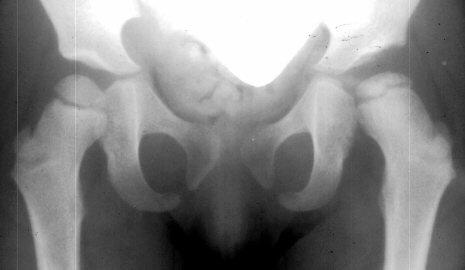

Four months later, the spica cast was removed and an Atlanta brace was applied. X-rays showed avascular necrosis at ten months of age . At two years of age, the ossification of the left nucleus was still delayed. The leg lengths were equal and the range of motion of the hip was full.

The progression of the hip is documented by x-rays taken at 1 year of age, 2 years of age, 3 years of

age, 5 years of age, 7 years of age, then at ten years of age, early closure of the lateral portion of proximal growth plate observed. Coxa valga was also observed.